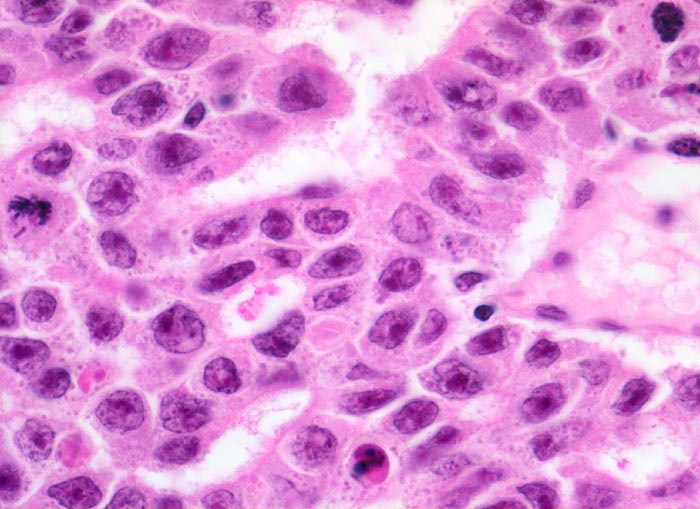

Histologisch bilden die Tumorzellen solide Zellplatten, Drüsen oder papilläre Strukturen mit Einblutungen und Nekrosen. Die Tumorzellen sind polygonal, kubisch oder zylindrisch, haben reichlich Zytoplasma und unscharfe Zellgrenzen. Die grossen Kerne haben grob verklumptes Chromatin und enthalten oft mehrere sehr grosse unregelmässige Nukleolen. Gefässeinbrüche und eine testikuläre intratubuläre Neoplasie sind in der Tumorumgebung häufig nachweisbar